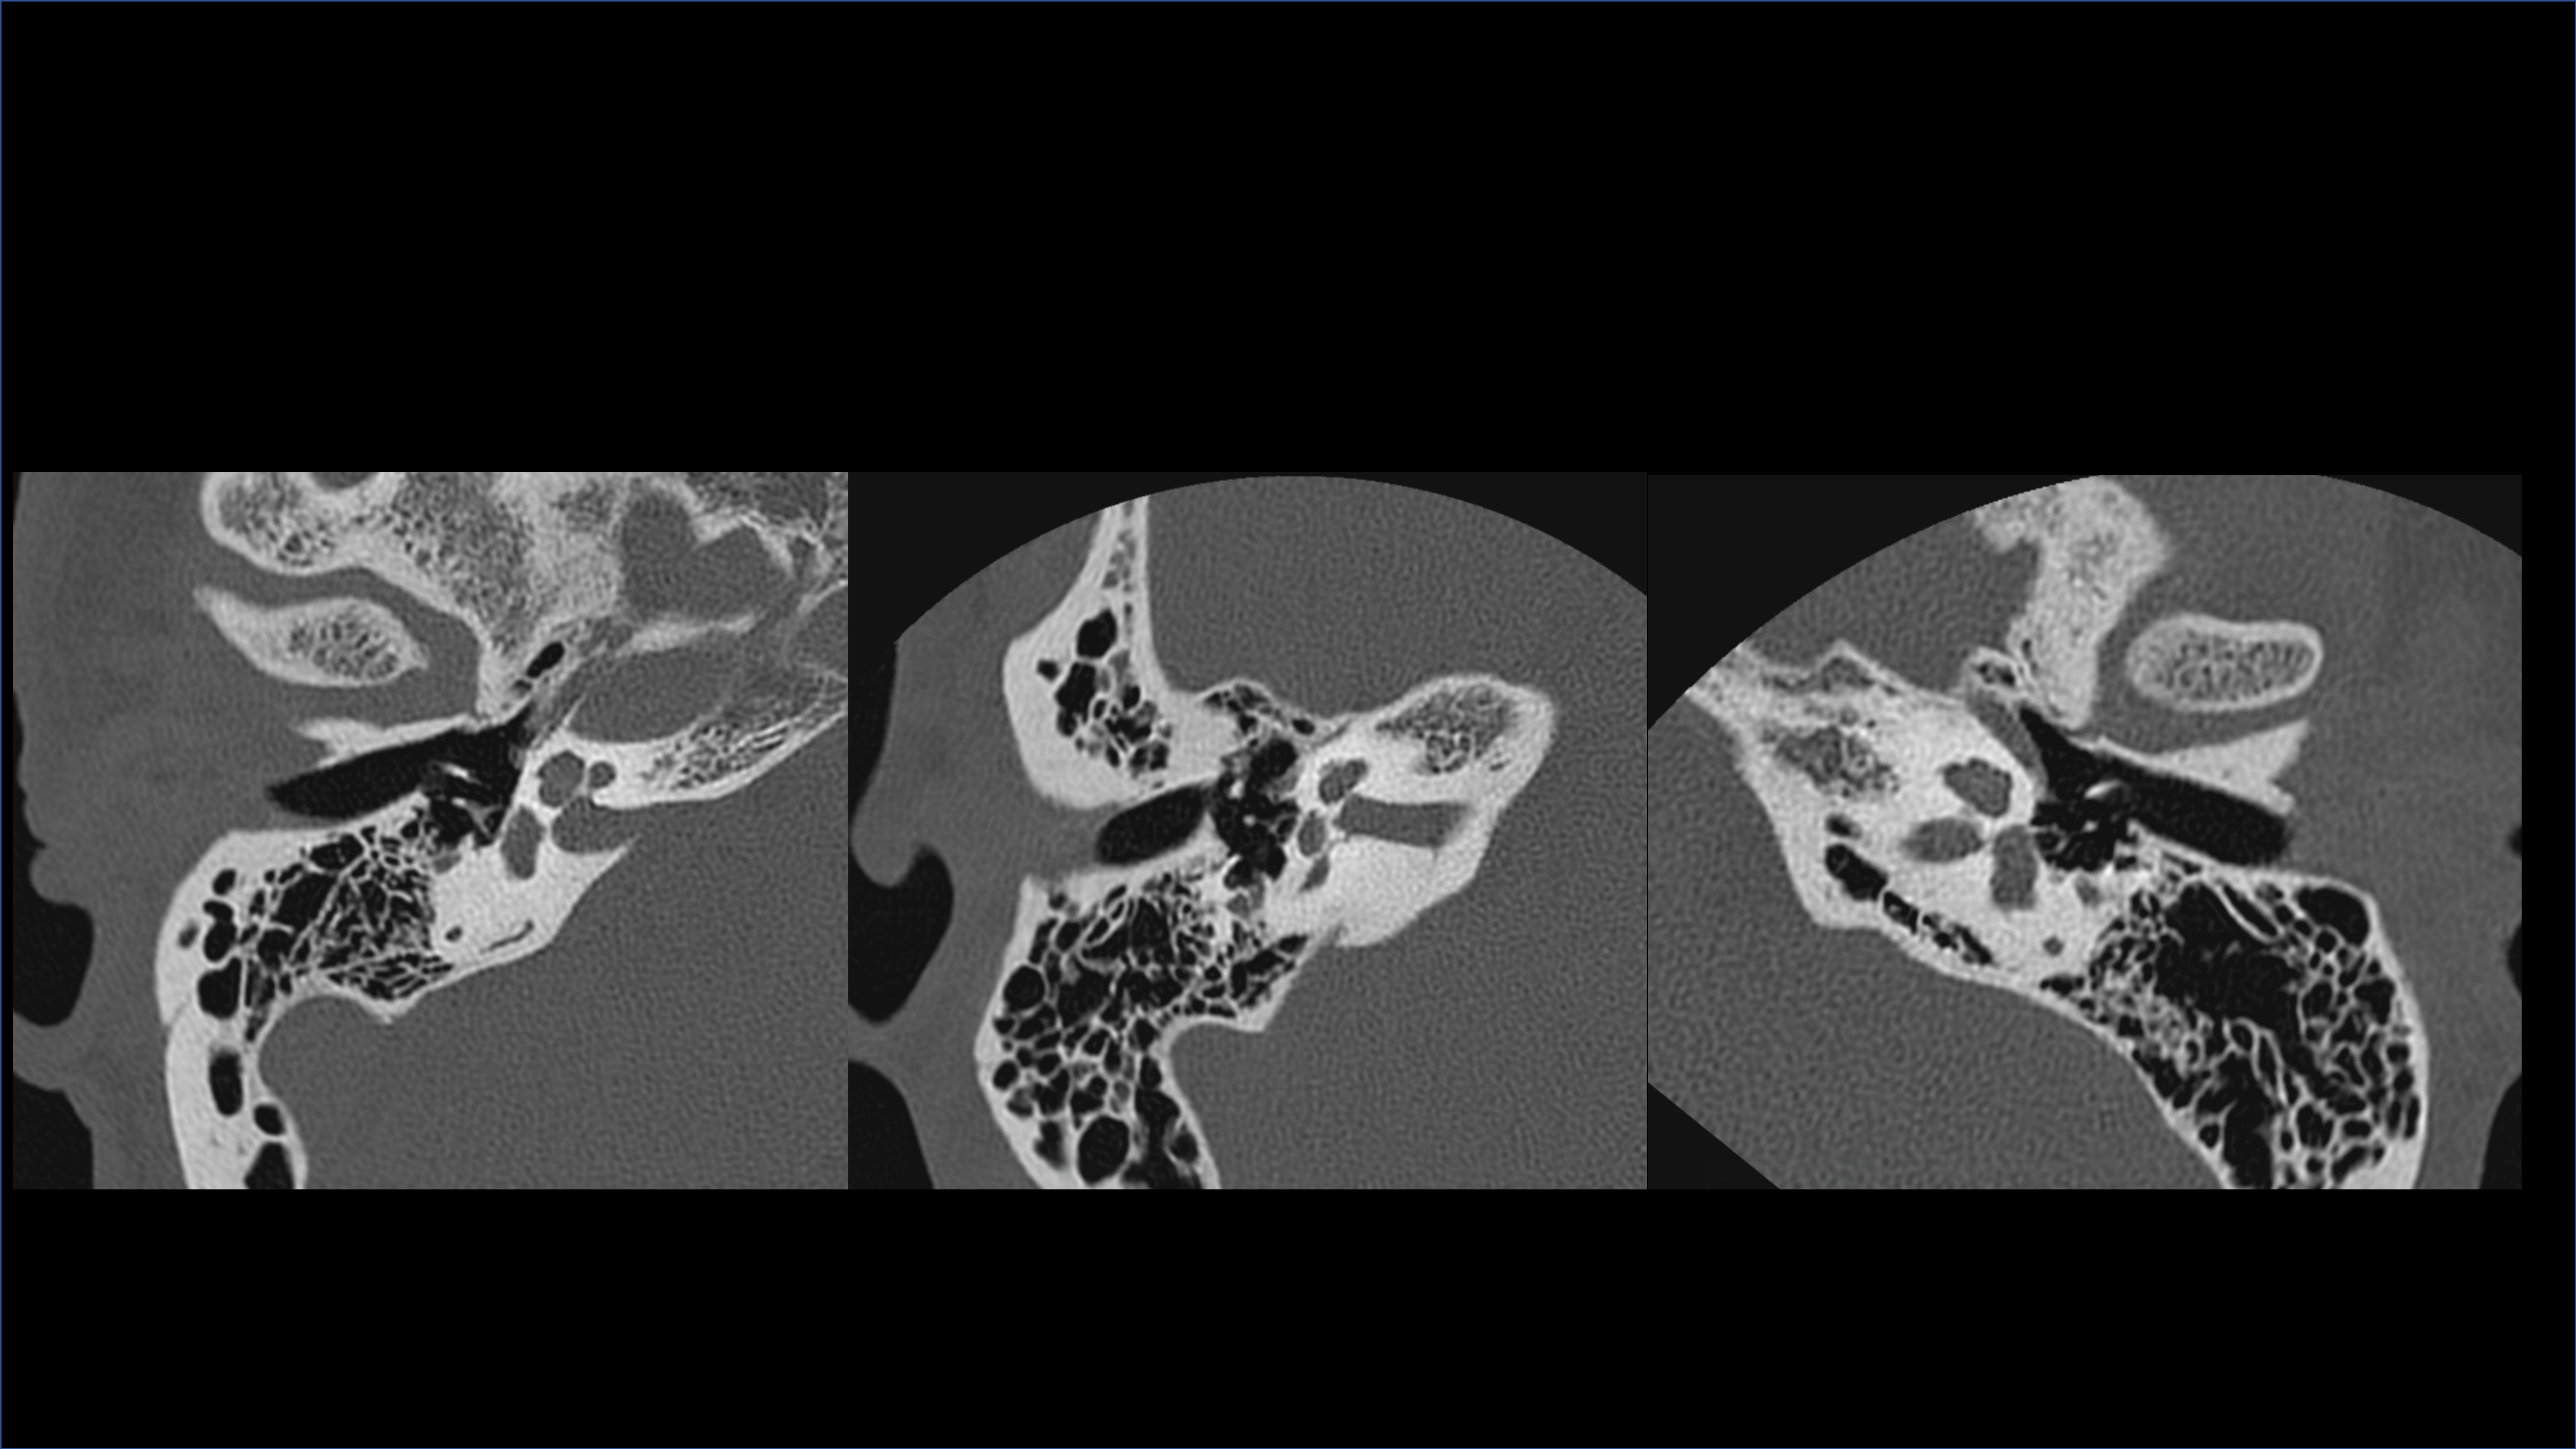

Delivers extraordinary spatial detail for confident, accurate diagnosis.